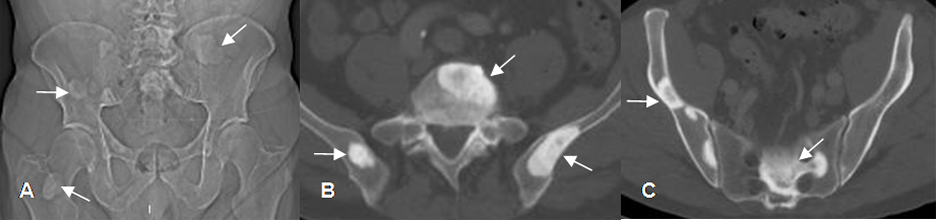

Fig 223. Metástasis blásticas.

A: Rx AP, B y C: TAC axial. Múltiples lesiones densas en los huesos iliacos, columna y fémur derecho, por metástasis blásticas de neoplasia pulmonar.